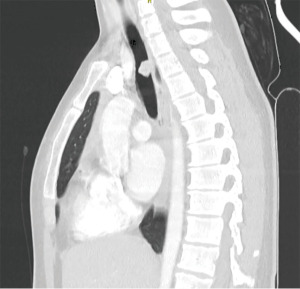

A 14-year-old active male with a previous medical history of reflux, asthma, adenotomy and ear tube placement presented with symptoms of dyspnea and hemoptysis during physical activity. Diagnostic workup included a CT-scan, which showed a polyp-like mass in the middle third of the trachea (Figure 1A,1B). A thickening of the tracheal wall was seen at the level of the mass, which occupied more than 4/5 of the lumen, resulting in a near-total tracheal obstruction. There were no clearly involved lymph nodes or associated pulmonary or bone lesions identified on imaging. The maximum diameter of the mass was 11 mm. Lung function testing showed a flow volume loop indicative of central airway obstruction (Figure S1).